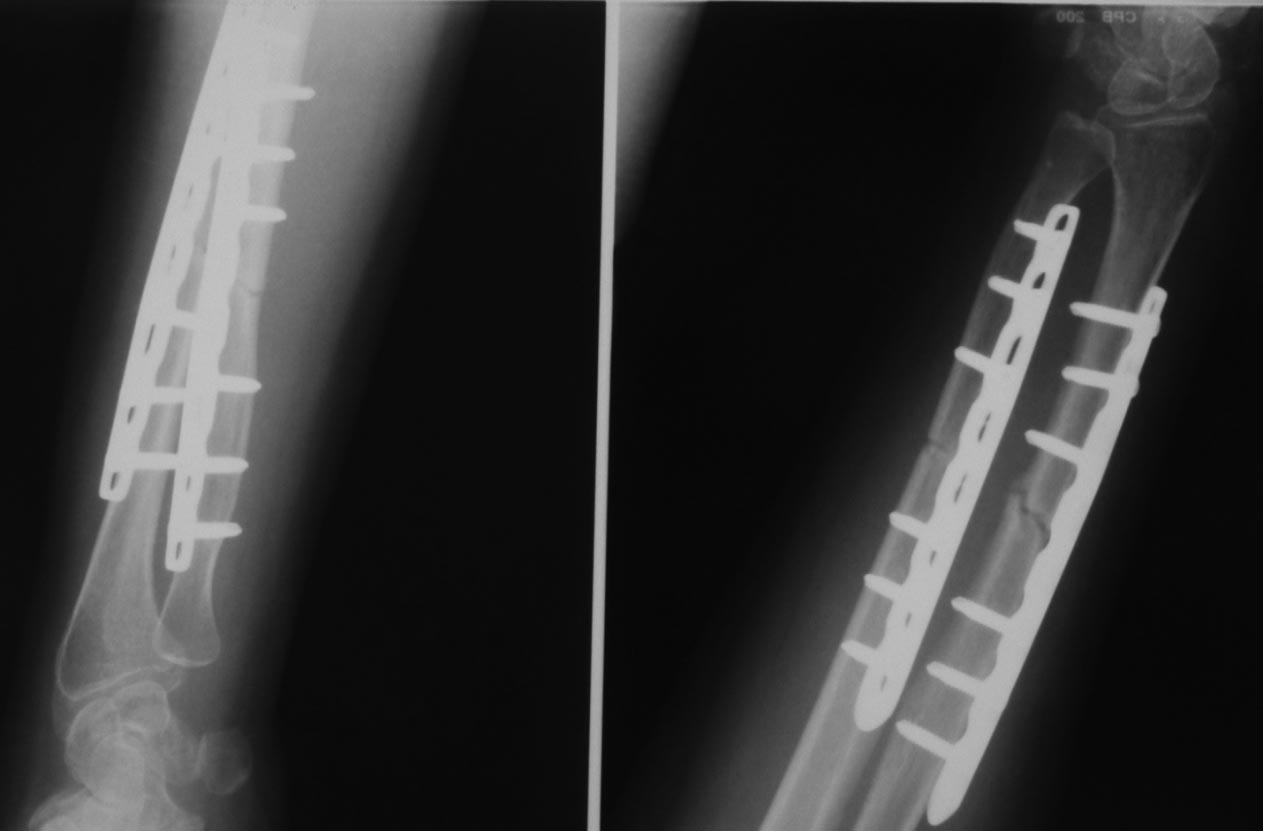

Пациентка 45 лет прооперирована по поводу перелома костей предплечья 26.01.12. Послеоперационый период гладкий, функция предплечья восстановилась. 12.05.12 упала повторно (обморок).

Диагностирован перелом головки локтевой кости. На мой взгляд, имеется и перелом по ходу дистального винта лучевой кости (появилось разрежение вокруг винта, которого не было на рентгенограммах через 1.5 мес. после операции). Хотя, локальной болезненности в этом месте нет. Болит в проекции кистевого сустава.

Вопрос: показано ли удаление этого винта? Не будет ли он препятствовать консолидации?